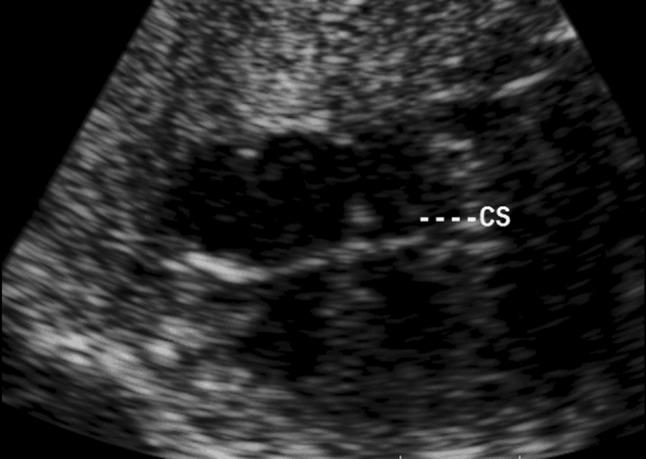

Comparison of coronary sinus diameter Z-scores in normal fetuses and fetuses with persistent left superior vena cava (PLSVC).

To establish Z-score reference ranges for coronary sinus (CS) diameter in normal fetuses and explore the diagnostic value of CS Z-score in fetuses with persistent left superior vena cava (PLSVC). Study of 235 normal fetuses and 30 fetuses with PLSVC was involved. Noncardiac biometrical parameters included biparietal diameter (BPD), femoral length (FL), heart area (HA), gestation age (GA). The coronary sinus systolic and diastolic diameter (CSDs and CSDd ) were measured at the end of systole and diastole. CSDs and CSDd Z-score models were constructed by using linear regression analysis with Non-cardiac biometrical parameters as independent variables. Z-scores between normal fetuses and fetuses with PLSVC were compared. A simple, linear regression model was the best description and correlations between fetal CSDs and CSDd and four independent variables were excellent. Reference ranges for predicting means and SDs of the fetal CS were established. Equations for Z-score calculation were provided, CSDs and CSDd Z-scores were statistically different between normal fetuses and those with PLSVC. Development of CSDs and CSDd Z-score reference ranges in normal fetuses was realized. The CSDs and CSDd Z-scores can provide quantitative evidence in prenatal diagnosis of PLSVC.